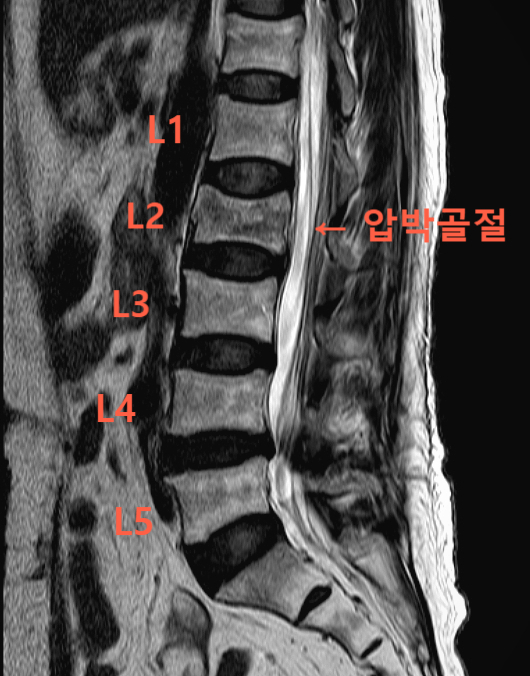

진단명 : 제2요추 골절 (S32030)

위 MRI 영상을 보면, 요추 2번이 찌그러지며 압박골절의 형태를 띠는 것을 확인할 수 있습니다. 환자분은 고령의 나이에다가 골다공증까지 심한 상태였으나, 다행히 비교적 안정형 골절의 양상을 보였는데요.

그래서 시멘트 시술은 시행하지 않고, 보조기 착용한 상태로 2달간 침상 안정을 취하는 보존적 치료가 행해졌습니다. 간혹 MRI 상으로는 신경 침범 소견이 안 보이더라도, 지속적인 통증을 호소하는 분들이 있는데요.